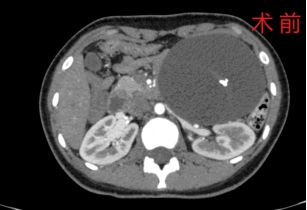

胰胆外科孔瑞主任医师接诊该患者后进行了详细的术前检查,发现这个巨大的肿物位于左上腹部,周围毗邻胰腺体尾部、横结肠、左肾、左肾上腺、小肠等重要脏器,肿瘤起源不确定,考虑来源于胰腺的可能性大。

经过细致的术前准备和充分的沟通,孔瑞主任医师和胡继盛主治医师团队为小女孩实施了腹腔镜探查手术。术中镜下探查发现胰腺体尾部下方有一大小约为13cm×10cm×7cm的巨大囊性肿瘤,肿瘤与周围脏器粘连严重,充分游离粘连后发现肿瘤与胰腺关系十分密切,考虑为胰腺囊性肿瘤。由于患者年仅16岁,术中与家属沟通后决定行腹腔镜下保留脾脏的胰体尾切除术(Kimura法)。